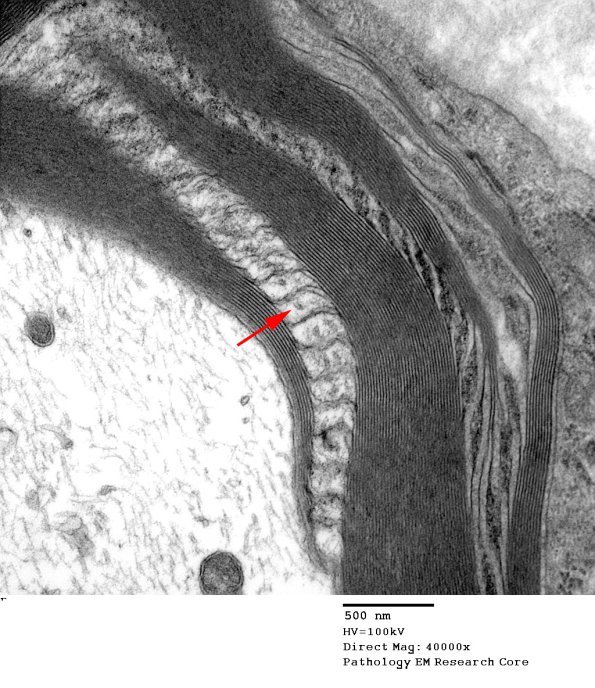

Higher magnification of image #4A3 showing a single microtubule (arrow). (electron micrograph)